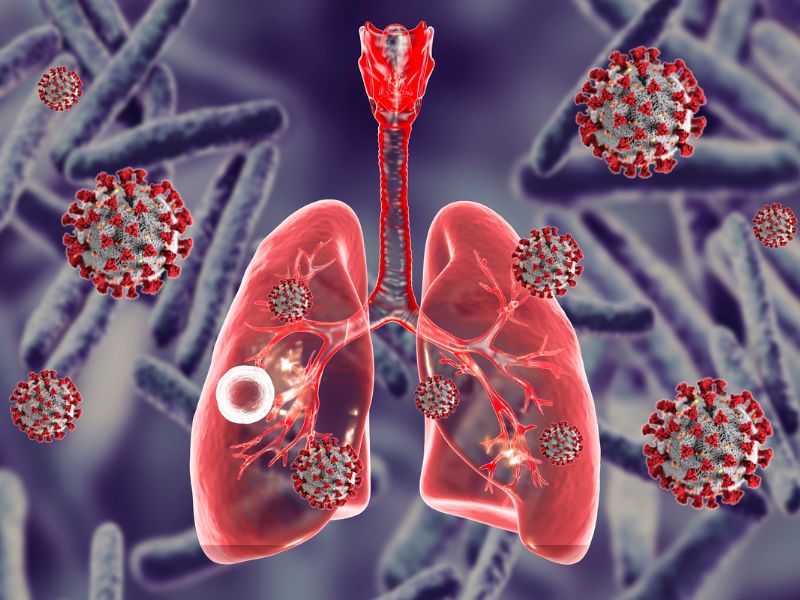

Tuberculosis

Tuberculosis TB is caused by the bacterium Mycobacterium tuberculosis. The germs are spread through the air and usually infect the lungs, but can also infect other parts of the body.

How Has The COVID-19 Pandemic Affected Tuberculosis Eradication?